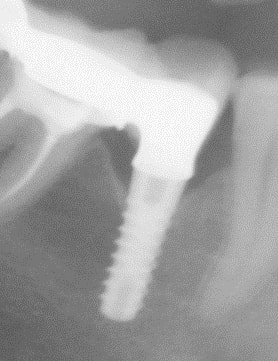

une rétro stp!!!!!

il me semble deviner un évent apical et un col sans spires....si oui, moi je pencherais plus pour çà...

Je pense que mon implant est a conexion externe, avec un col droit sans spires.

La forme evasée du col je pense qu' elle fait partie de la prothése.

Sur l' apex je pense qu'il y a une echancrure, mais pas de trou.